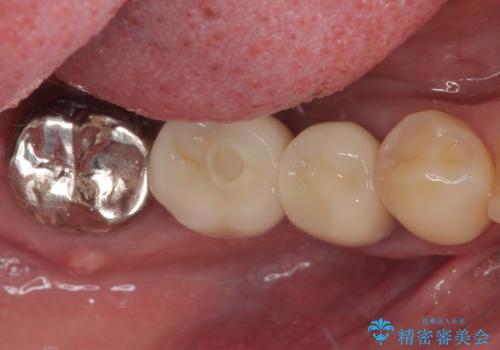

右下は大臼歯部の歯は抜歯即時埋入インプラントにて、手前の歯は保存して補綴治療を行うこととしました。

インプラント埋入時に十分な安定値を得ることができたため、速やかに仮歯を装着し、最小限の通院回数で治療を終えることができました。